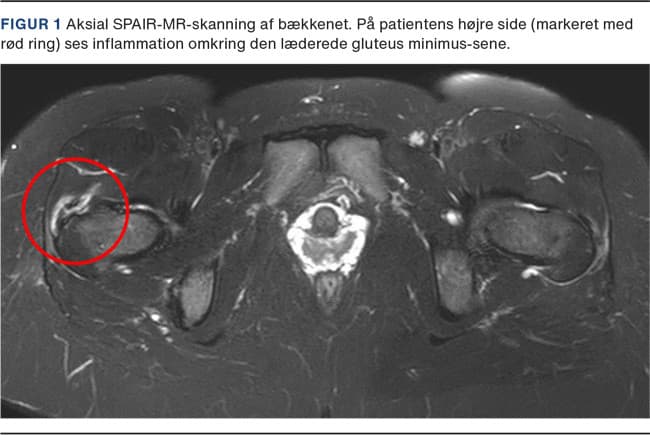

Vi fandt ved objektiv undersøgelse svær palpatorisk ømhed i trochantermassivet, positiv 30 s etbensstand (hvilket udløste kendte smerter) samt nedsat kraft mod tyngden ved sideliggende abduktionstest. Der blev ikke fundet smerter, som var forenelige med labrumskade. Patienten blev henvist til MR-skanning af bækkenet uden kontrast på mistanke om skade på glutealhæftet. Skanningen viste forandringer, som var forenelige med en skade på gluteus minimus-senen (Figur 1). Hun gennemgik operation, hvorunder der fandtes total ruptur af gluteus minimus. Gluteus medius-hæftet var uden skade. Ved operationen blev gluteus minimus refikseret til sit footprint på trochanter major med to stk. 4,5 mm ankre.